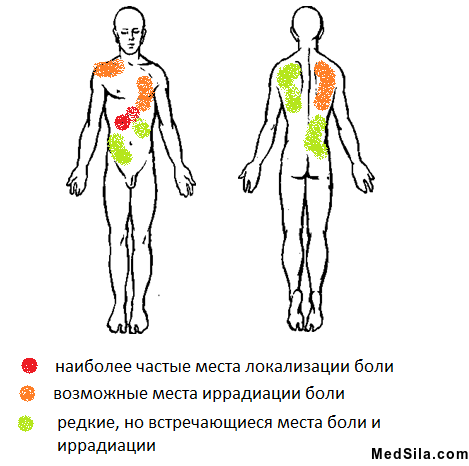

- боли в правом подреберье, иногда под «ложечкой», которые могут отдавать в правое плечо и под правую лопатку, редко в левую половину тела. Боли обычно тупые или тянущие и проходят самостоятельно или при приеме спазмолитиков через несколько часов, реже дней. Обычно они появляются при погрешности в диете: жареное, острое, соленое, копченое, употребление спиртных или газированных напитков; сильных стрессах или после чрезмерной физической нагрузки;

- острая боль в правом подреберье;

- кардиалгической: характерны боли за грудиной, больше похожие на сердечные, могут появиться различные формы аритмий;